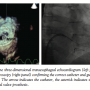

defect was considered to be possible. After transseptal puncture in the basal area of the septum, an 8.5 Agilis NXT medium-curve steerable sheath was advanced across the septum with its tip positioned near the defect. A 5 Fr JR coronary catheter was telescoped within the Agilis sheath for additional steering capacity. Under guidance of real-time 3D TEE, the coronary catheter could be advanced close to the defect. Subsequently, an angled 260 cm Terumo Glidewire allowed crossing the defect (Figure 3). The coronary catheter was advanced into the left ventricle over the wire. The wire was exchanged for a 260 cm Amplatzer extra-stiff wire. This wire gave enough support to advance a 9 Fr guiding catheter through the paravalvular defect. A 14 x 5 mm Amplatzer Vascular Plug III (St Jude Medical) was advanced through the 9 Fr guiding catheter

and sandwiched the defect effectively. 3D TEE confirmed the stability of the device, complete closure of the defect (Figure 4), adequate movement of both discs of the mitral valve prosthesis, and almost complete reduction of mitral regurgitation.